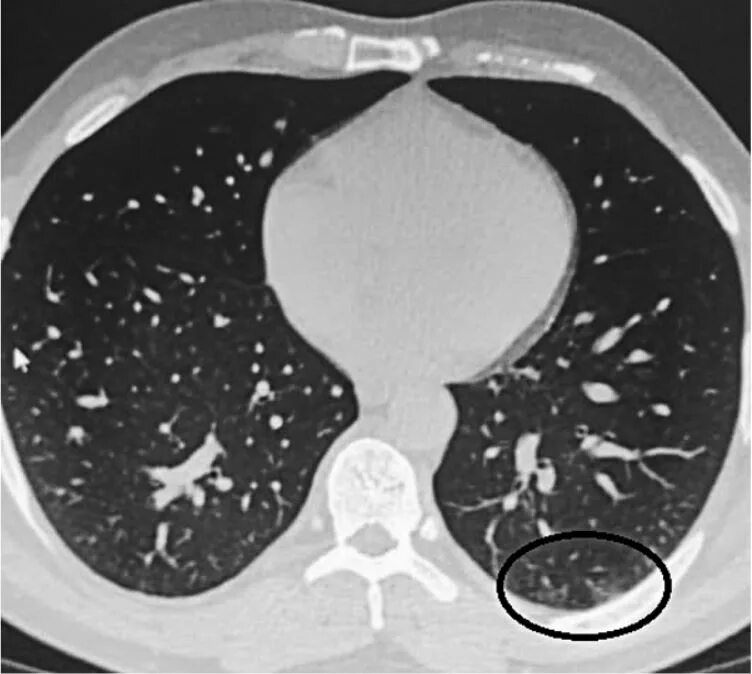

Как выглядит пневмония на кт